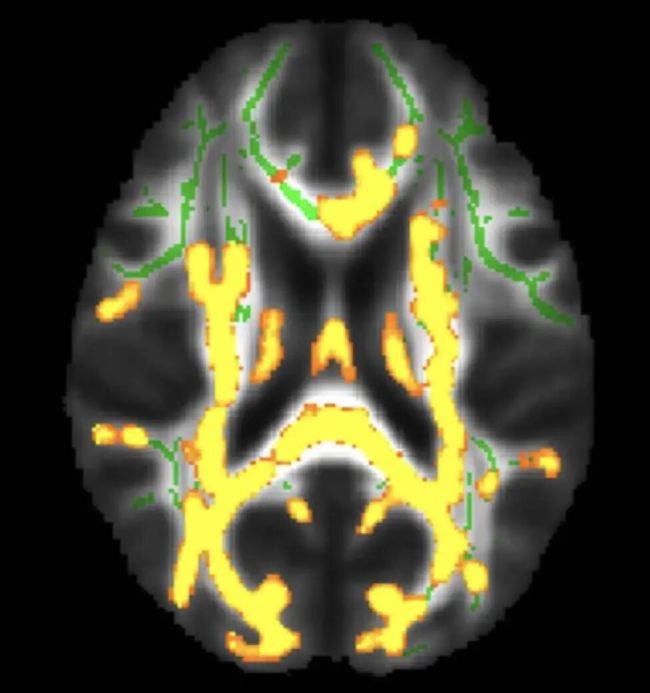

脑部扫描显示隐藏的内脏脂肪水平较高,神经炎症(黄色)增加